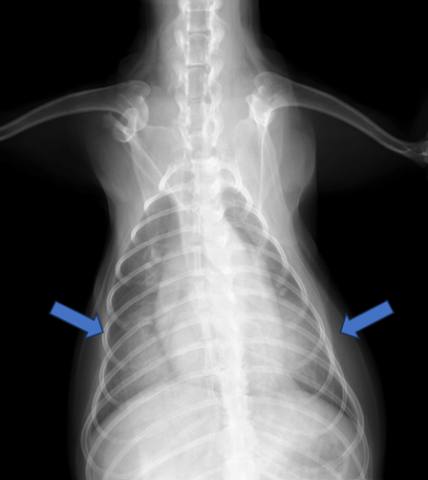

胸部レントゲン検査にて心陰影の拡大と肺野の透過性の低下が認められました。

既往歴と画像所見から僧帽弁閉鎖不全症ステージCへの進行による心原性肺水腫と診断しました。